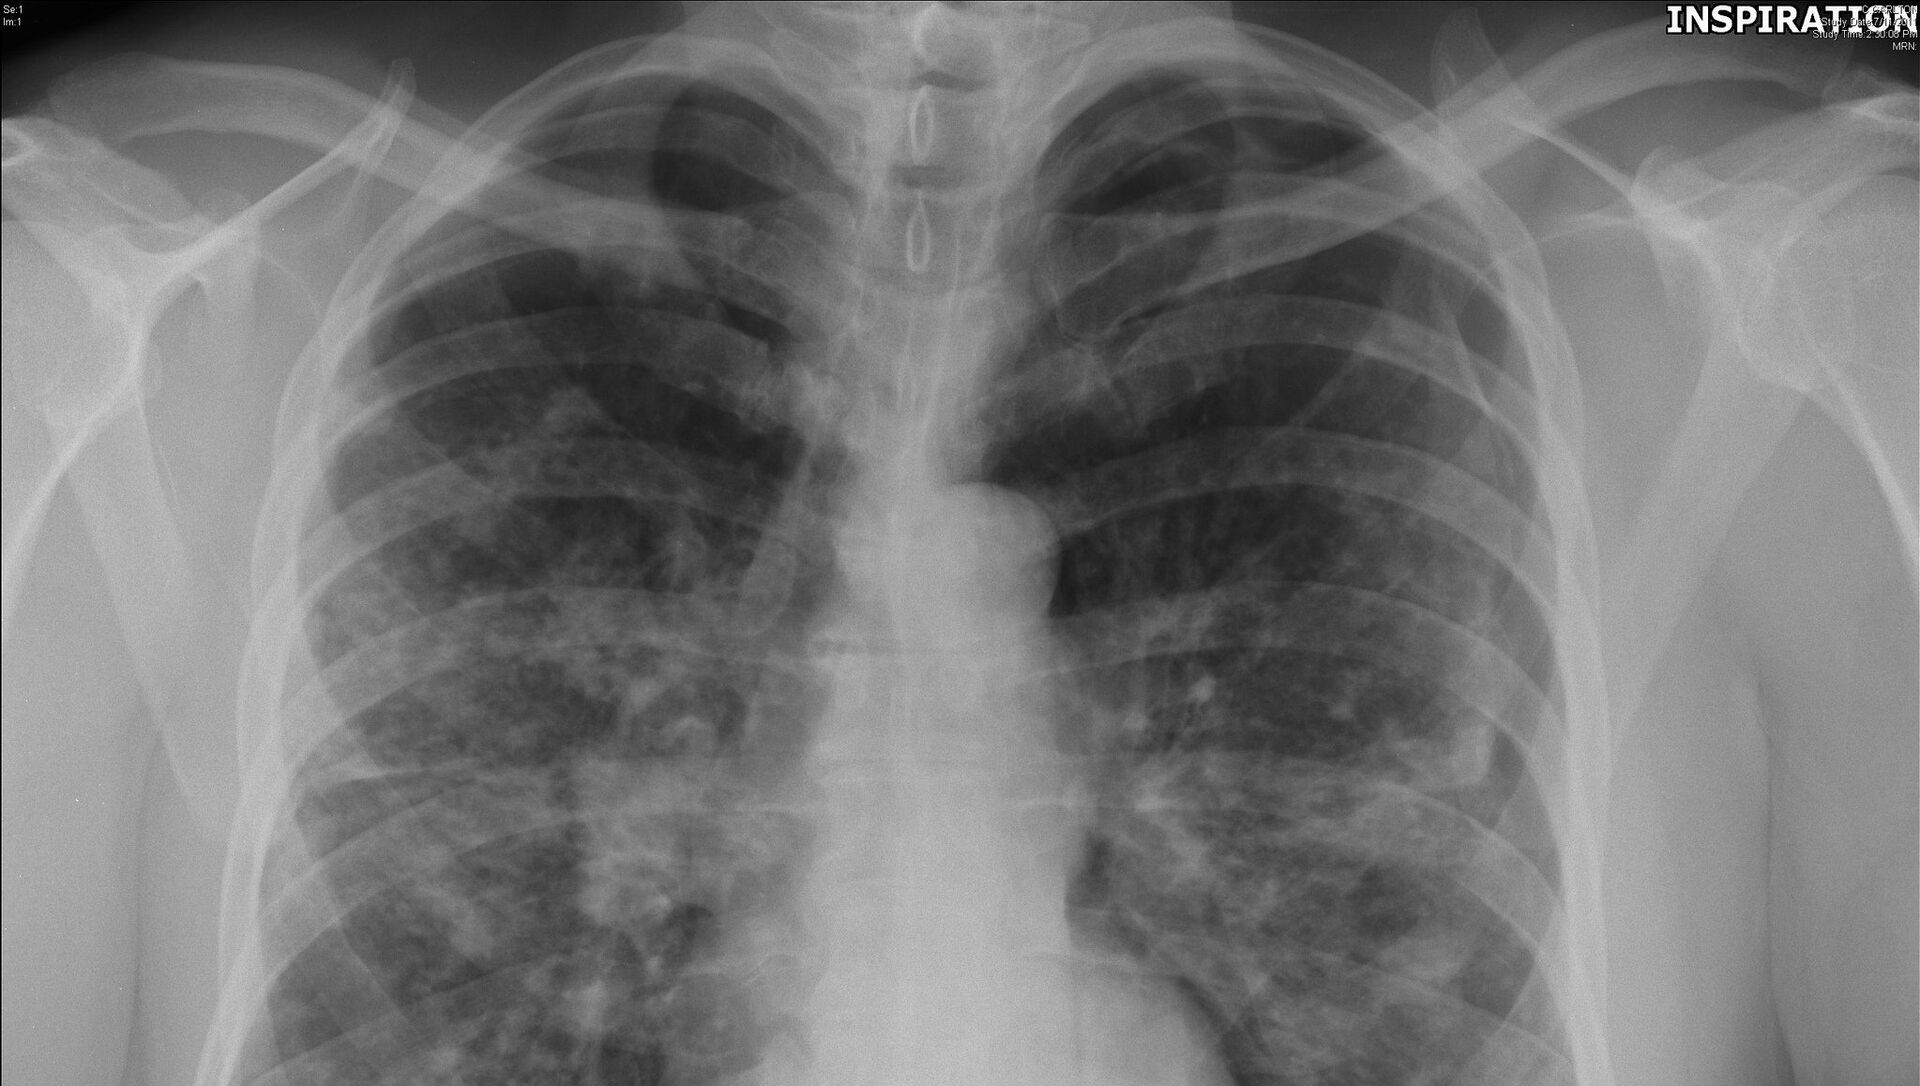

Este nuevo sistema puede ayudar a detectar el cáncer de pulmón de una manera rápida, eficiente y no invasiva, algo que hasta ahora era imposible.

El cáncer de pulmón es uno de los más mortíferos entre las enfermedades cancerosas. En Rusia se registran unos 60.000 casos de cáncer de pulmón al año. Y la posibilidad de detectarlo a tiempo podría ser la diferencia entre la vida y la muerte.